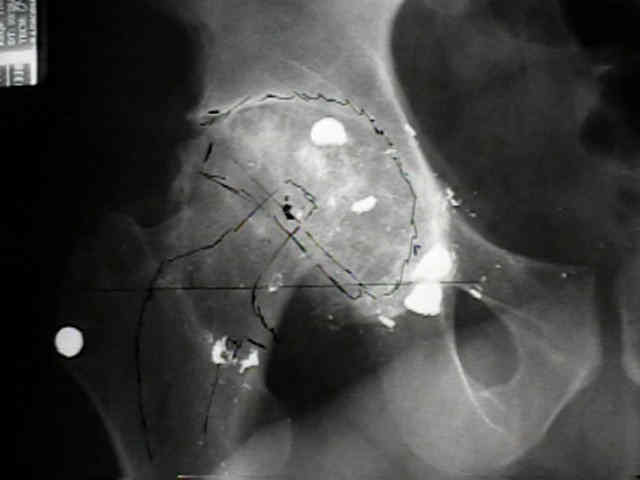

Case Example

- 35-year-old male w/ near anklyosed hip following a GSW to the hip;

- preoperative films appeared to indicate that little or no medialization was necessary;

- postoperative films, however, indicate that the cup was lateralized (hence, reaming was inadequate);

- in retrospect, the radiographs which are rotated externally (like an iliac oblique) tend to falsely minimize the necessary amount of medialization where as X-rays which are rotated internally (like an obturator oblique), tend to over-estimate the necessary amount of medialization